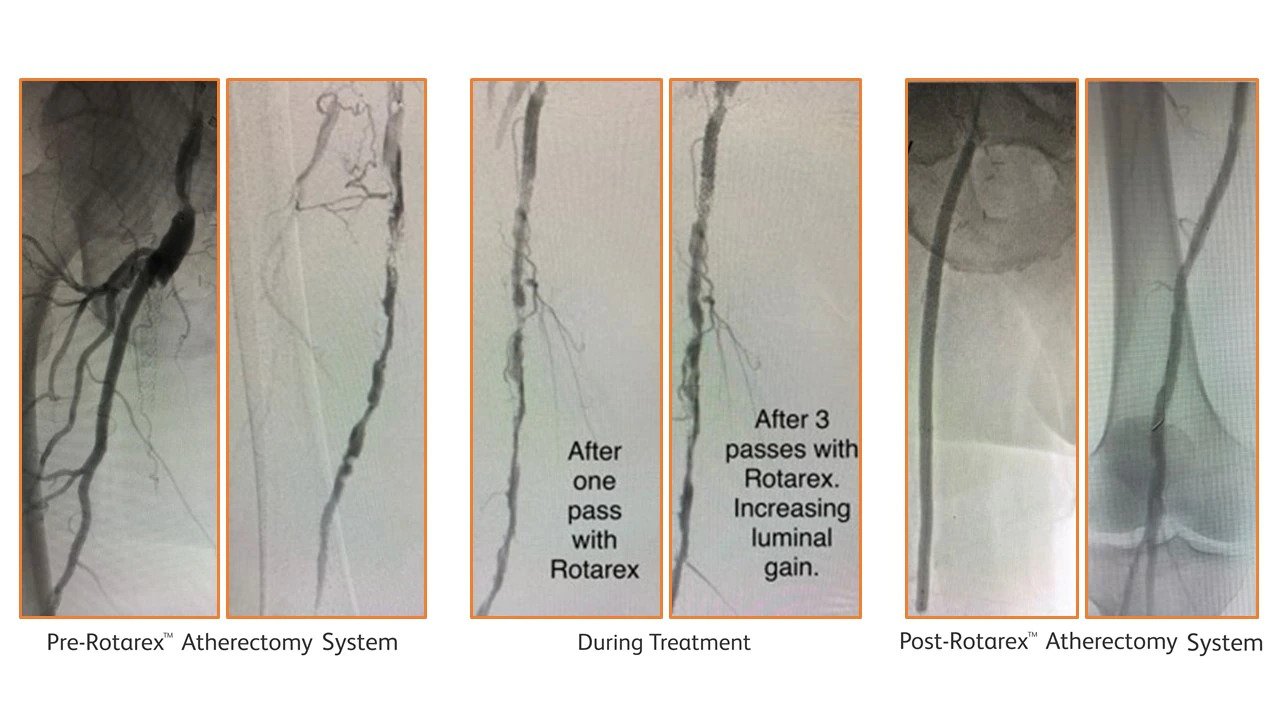

Chronic total occlusion of the superficial femoral artery

Dr. Bruno Freitas, MD, Prof. Santa Casa de Marveió, Federal University of Alagoas2

64-year-old male patient presented with left-sided CLI. Over the preceding four months the patient experienced left-sided rest pain and despite receiving best medical treatment, developed a dry, non-healing ulcer of the toe. Puncture of the right groin and cross-over approach, demonstrated a very long, 31 cm, TASC D, femoropopliteal CTO on angiogram. The SFA occlusion was recanalized with a wire intraluminally, followed by 3 passes of a 6F Rotarex S™ Atherectomy Catheter, after which 3 PTAs resulted in a completely restored flow. The patient remained asymptomatic after 18 months.

<h3>Before treatment, Flush occlusion of left SFA to PII segment. Crossed intraluminally with guidewire.</h3>

Before treatment, Flush occlusion of left SFA to PII segment. Crossed intraluminally with guidewire.

<h3>Extensive collaterals of SFA reconstituting at PII segment, with 2 vessel run-off BTK.</h3>

Extensive collaterals of SFA reconstituting at PII segment, with 2 vessel run-off BTK.

<h3>Angiogram after 1 and 3 passes with Rotarex™ Atherectomy Catheter.</h3>

Angiogram after 1 and 3 passes with Rotarex™ Atherectomy Catheter.

<h3>Final angiogram showing restored flow in SFA and 3 vessel run-off BTK.</h3>

Final angiogram showing restored flow in SFA and 3 vessel run-off BTK.